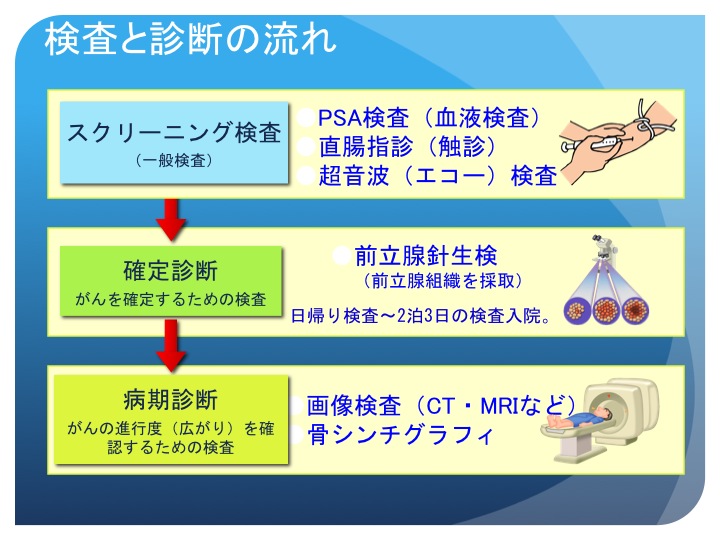

検査の流れ 50歳を過ぎたら注意 前立腺がん 患者 ご家族の皆様

確定診断までの流れ がんの治療法 詳しく知りたい 前立腺がん

確定診断までの流れ がんの治療法 詳しく知りたい 前立腺がん